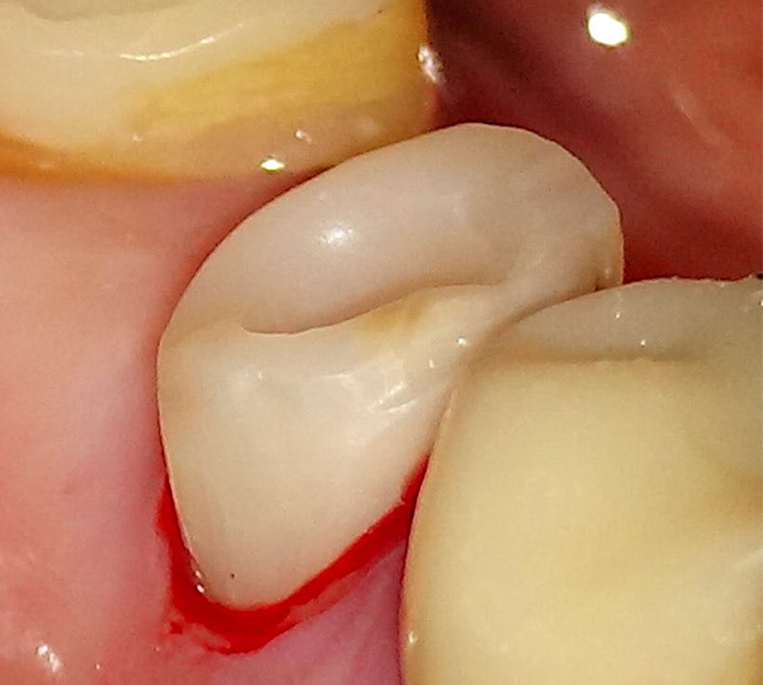

被せ物除去

この写真のように、被せ物に隠れて虫歯(黒い部分)が進行していることが多々あります。